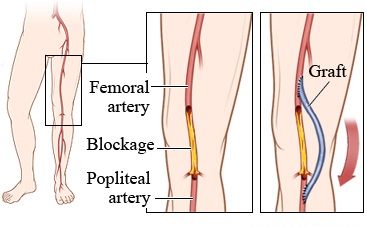

Overview

Package includes:

Days in hospital : 7 to 8 Days (For patient and one attendant)

Days in hotel : 14 Days (For patient and one attendant)

Room type in hospital : Shared

Room type in hotel : Private

Hotel category: Standard

Value added benefits of the Femoro Popliteal Bypass:

Ø Doctor consultation charges

Ø Lab tests and diagnostic charges

Ø Room charges inside hospital during the procedure

Ø Surgeon Fee

Ø Nursing charges

Ø Hospital surgery suite charges

Ø Anesthesia charges

Ø Routine medicines and routine consumables (bandages, dressings etc.)

Ø Food and Beverages inside hospital stay for patient and one attendant.

Extra benefits:

ü Interpreter

ü Visa assistance

Ø Site tourism of the city

Ø Follow up with the doctor

Ø Airport pick up and drop

Ø Free online consultation with the doctor

Ø Priority appointments with the doctor

Ø Room upgrade from sharing to private